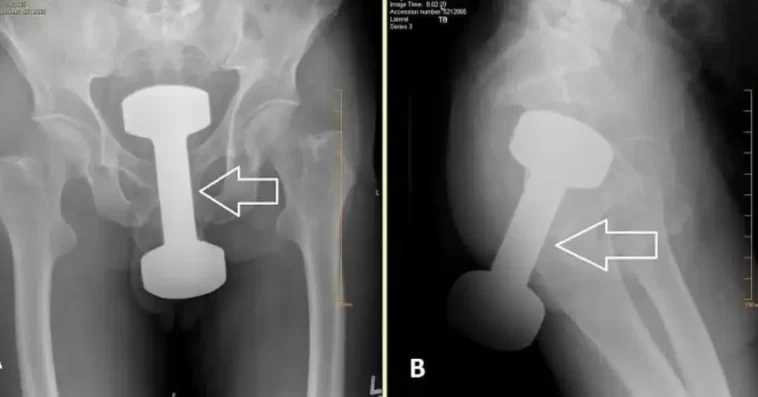

A local doctor in the country recently shared this; a 2.5KG dumbbell… The patient preferred not to disclose how it occurred.

A local doctor in my country just shared this surprising post about a 2.5KG dumbbell, as the patient was unwilling to explain how the incident occurred.

It went through their trousers & pants as well. Unless they were weight lifting naked, of course. Horrific accident… /s thought I better add this, just in case Also, the big white arrow! Cos you might otherwise have missed it